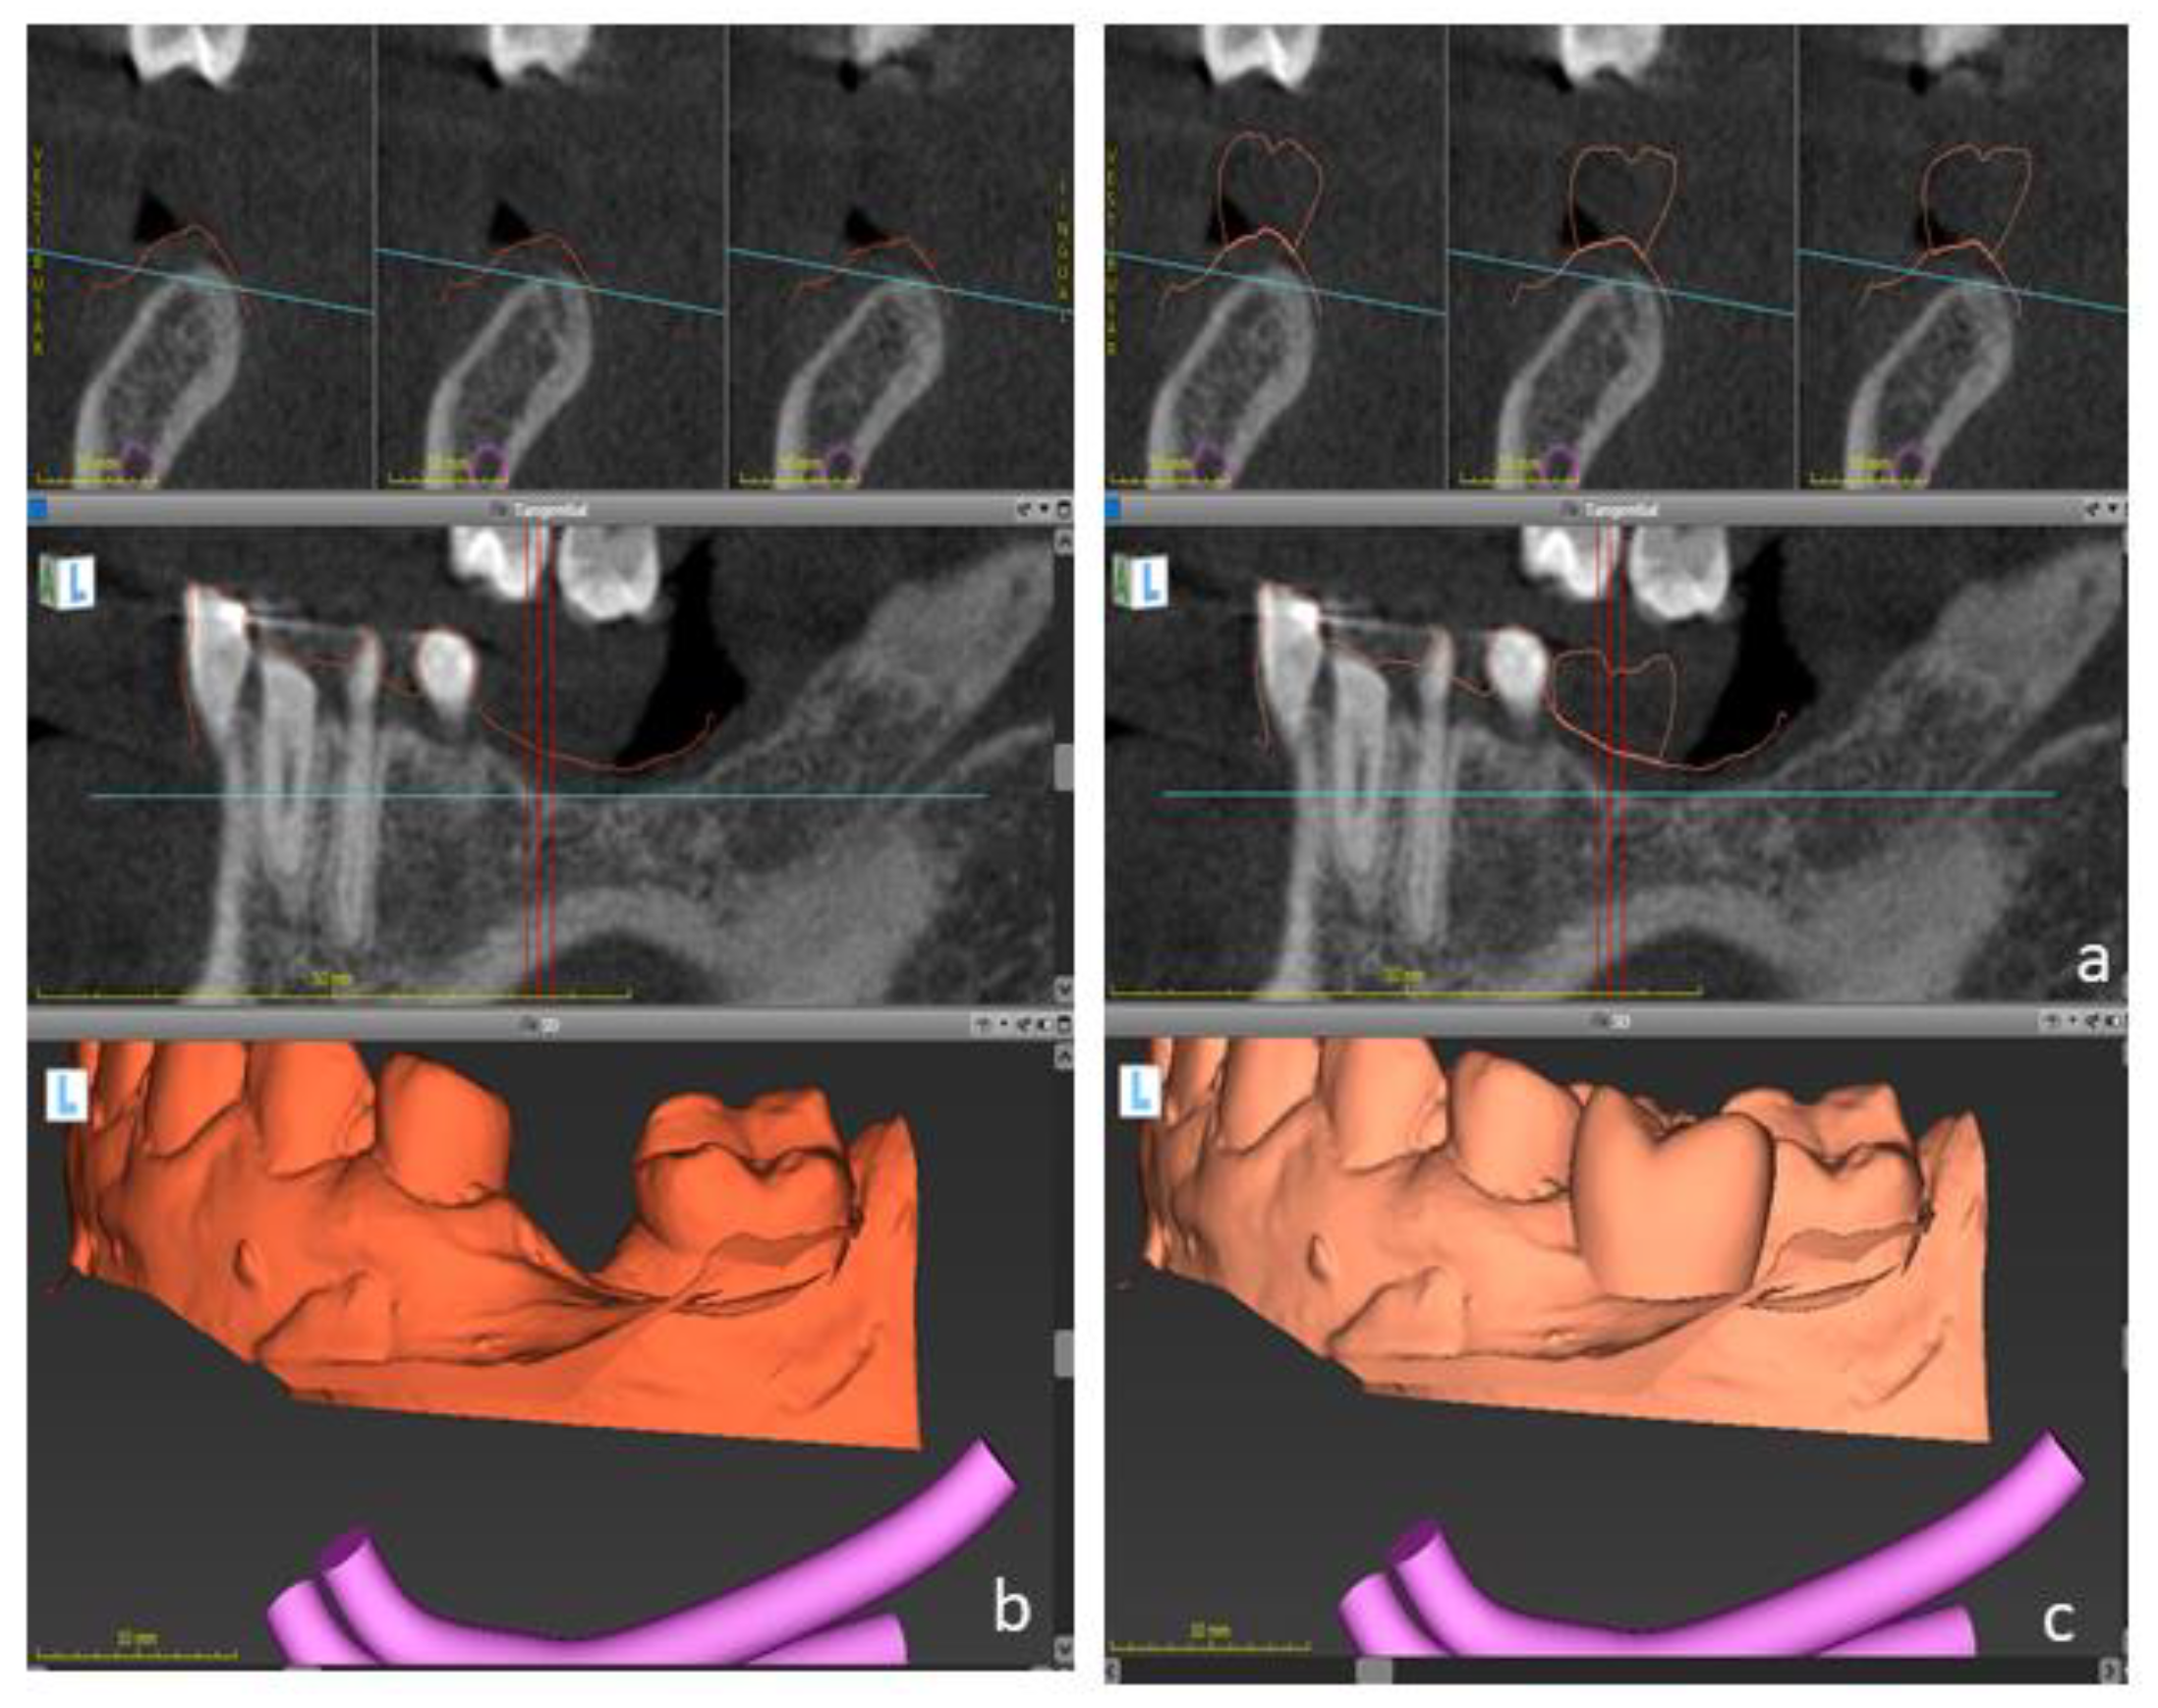

Figure 3.

Digital files were taken to the virtual planning using an implant planning software. DICOM files (a) were matched to dental casts (b) and to the digital wax-up (c) to determine the optimal implant position.

The digital planning is shown in Figure 3 and Figure 4. A cone-beam computed tomography (CBCT) image was taken from the lower jaw using a CBCT device (Kavo, Kloten, Switzerland). Intra-oral scans were taken using a three-dimensional (3D) scanner (3Shape). Digital planning was conducted by a dental technician using the software Co-DiagnostiX (Dental Wings, Montreal, QC, Canada).

In summary, the “digital imaging and communications in medicine “(DICOM) files were imported to the software, and segmented automatically to comprise the region of interest. Next, “standard tessellation language” (STL) files were imported and superimposed upon DICOM-Data based on common points, which were defined by the user. In addition, the digital wax-up was matched to these files. This approach enabled to plan the implant location, taking into account the bone anatomy and the planned restorations.

Dental implants with appropriate dimensions (size and length) were selected from the library offered by the software to simulate the implant position. In order to avoid inaccuracies caused by dental implants-based artifacts, STL-Data were used as reference to determine the teeth surface. A surgical guide was designed based on the digital planning and printed using a 3D-printer (Formlabs) to guide the surgery.